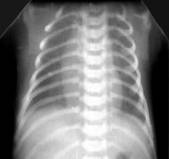

Умеренное снижение пневматизации легких, различимы воздушные бронхограммы, границы сердца чёткие (Рис.4).

Рисунок 4Рентгенограмма грудной клетки в прямой проекции в горизонтальном положении. (Диагностика и лечение РДС недоношенных // метод. Рекомендация, 2007)